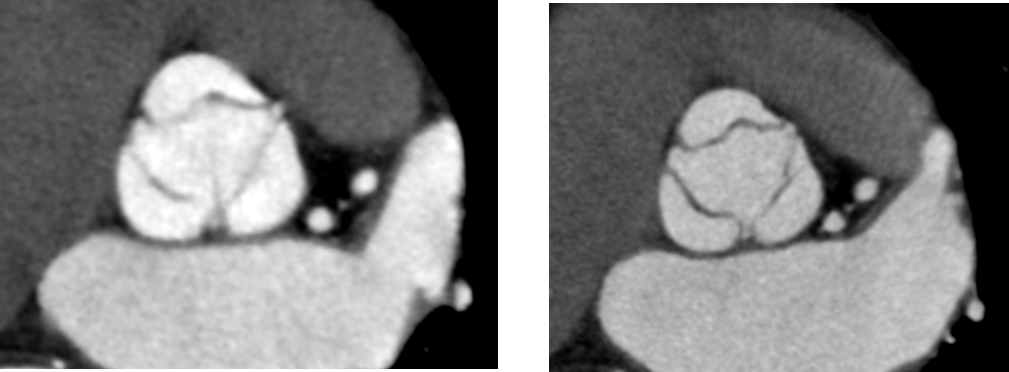

左側の従来のSSF2.0を使用していなかった際の画像は3心拍以上のvolumeデータを使用して再構成を行っているにも関わらず大動脈弁がぶれてしまっています。右側のAscend Eliteでは大動脈弁をしっかり描出できています。この画像はCT装置導入二日目にして得られたため、SSF2.0が冠動脈だけでなく弁にも有用であることが証明できた症例となりました。

Ascend_ayase02.png同一患者における画像の比較

(左:従来の検査データ)(右:Ascend Elite)